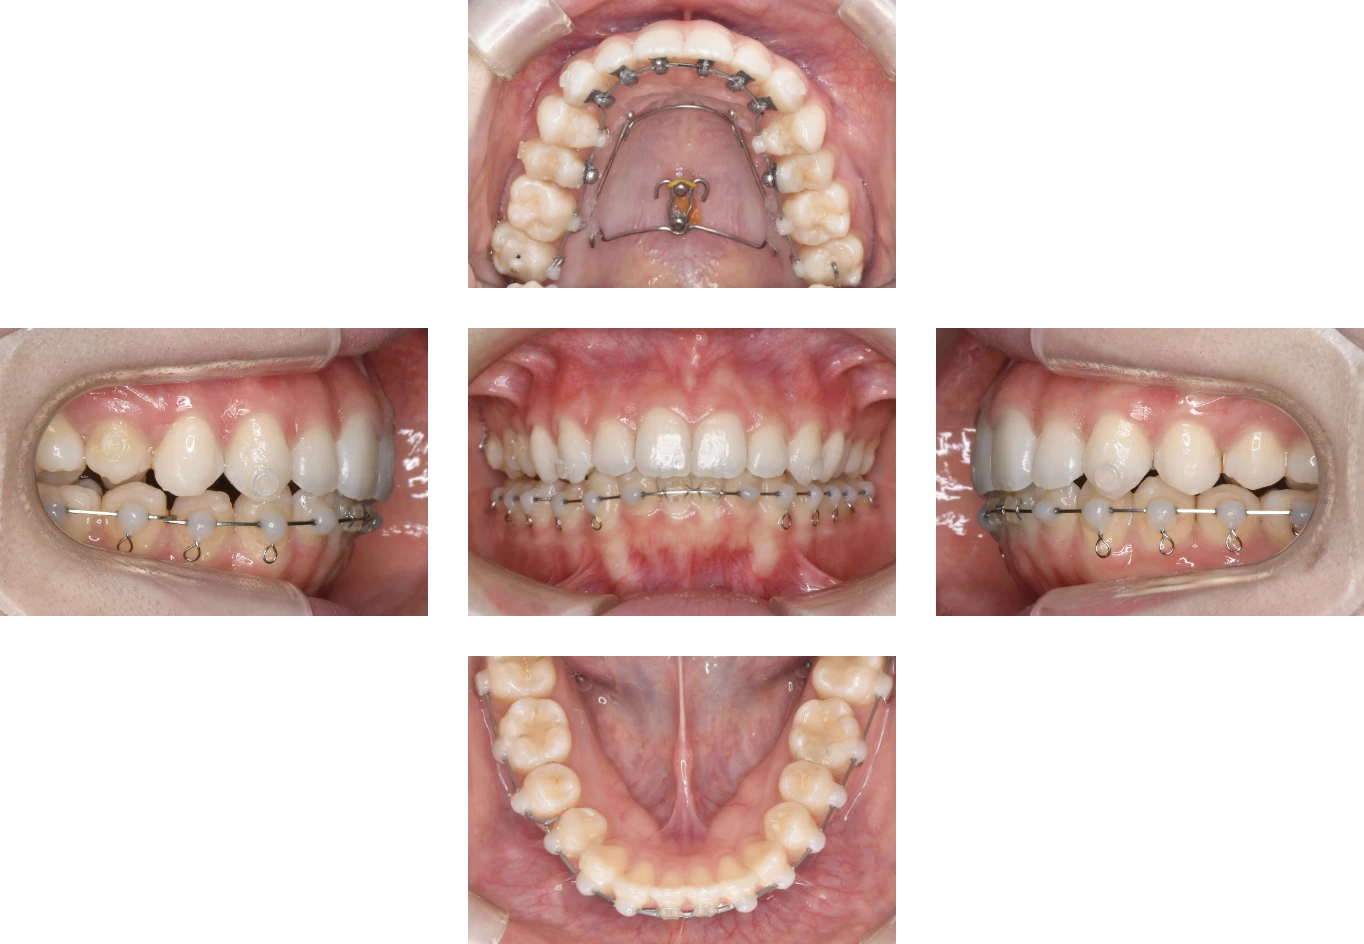

Case3

| 主訴 | 歯が出ているのが気になる |

| 診断名 | 上顎前突 |

| 年齢 | 16歳 |

| 治療に 用いた装置 |

リンガルブラケット矯正装置(エッグブラケット) |

| 抜歯部位 | 非抜歯 |

| 治療期間 | 2年5ヶ月 |

| 治療費用 | 1,385,100円 |